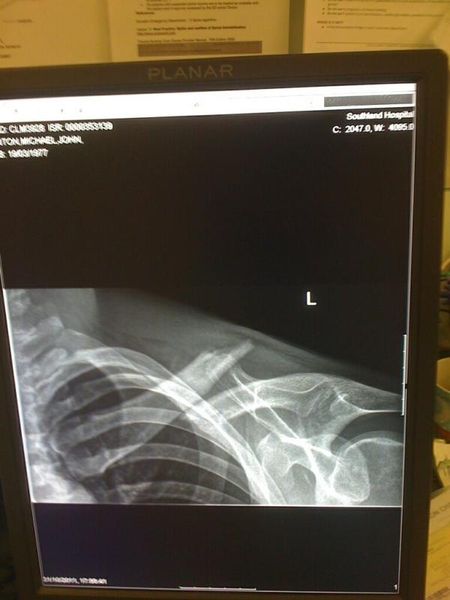

Henton rides through the pain barrier in Southland

By Daniel Simms published

New Zealander finishes stage after re-breaking collarbone